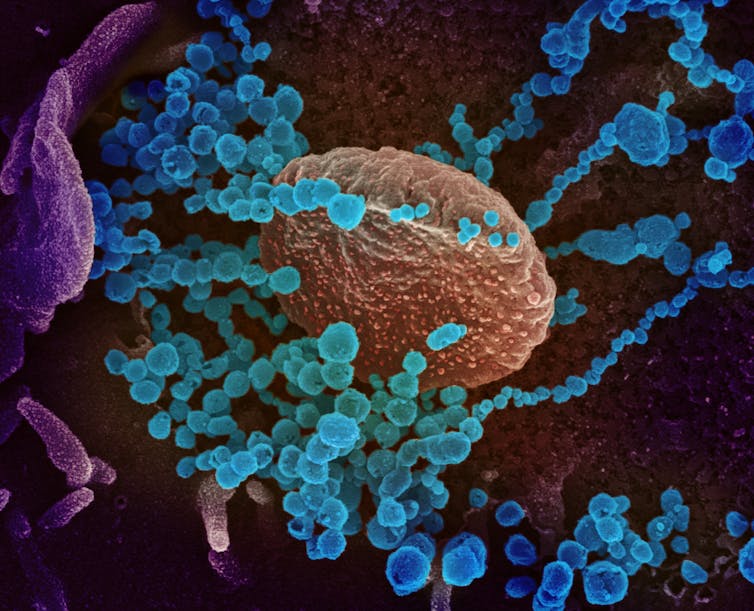

Les agents infectieux les plus connus à l’origine de pneumonies sont les bactéries. Ceci est lié non seulement à leur fréquence, mais aussi au fait que, contrairement aux virus, elles sont facilement mises en évidence au laboratoire par des techniques de culture standard, maîtrisées depuis longtemps. La culture des virus est beaucoup plus longue et difficile. En outre, leur petite taille implique de passer par des techniques de microscopie électronique pour les observer, lesquelles sont plus lourdes à mettre en œuvre que les techniques de microscopie optique utilisées pour les bactéries.

Selon les dernières revues de la littérature, les pneumonies virales représentent environ 20 à 25 % des pneumonies acquises en communauté(ou « pneumonies communautaires »), c’est-à-dire hors de l’hôpital, et jusqu’à 50 % dans les formes graves. Parmi les virus pourvoyeurs de pneumonies, les virus grippaux (Influenza virus), responsables d’épidémies hivernales, sont les plus connus. D’autres virus peuvent également être impliqués, comme le VRS (virus respiratoire syncytial), le rhinovirus ou encore les coronavirus.